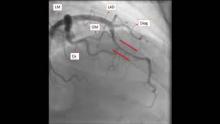

The authors present an interesting cases of a myocardial bridging as a cause of exertional chest pain. This is the case is of a 42-year-old woman with a past medical history of HTN and PAHTN who has been worked up by cardiology for chest pain with minimal exertion. The CXR didn’t show any acute abnormalities, and the EKG showed sinus rhythm with some indeterminate ST segment changes in the anterior leads. A normal EF of 60% was seen on the echocardiogram as well as a flattening ventricular septum consisting of right ventricular pressure overload. Due to her history of PAH, a right heart cath was performed, evidencing a severe pulmonary hypertension with baseline pulmonary artery pressures of 88/36. Finally, and as part of her workup, a left heart cath was performed, and there was evidence of codominance as well as an LAD and the mid-portion had a segment that was compressing during systole, concerning for myocardial bridging. This phenomenon can be clearly seen in the video.

Intramyocardial tunneling of a coronary artery can mimic myocardial ischemia, where the LAD is positioned intramuscular, different to the normal epicardial positioning of the coronary arteries. It is more frequent in females, and it is a benign finding. However, when symptomatic, myocardial bridging produces a decrease in the blood flow to the myocardium, when the vessel gets compressed during systole.